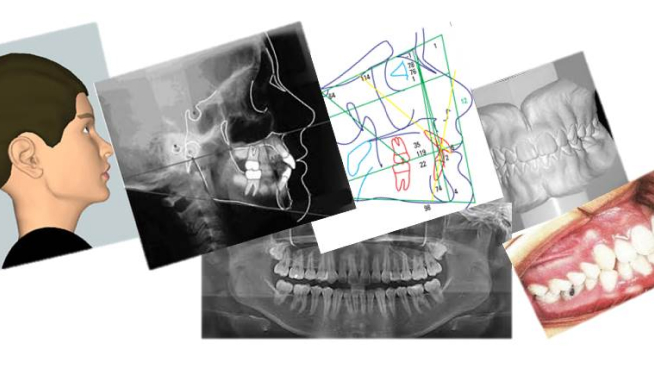

Documentações Ortodônticas

Radiografias Digitais com Laudos e Análises